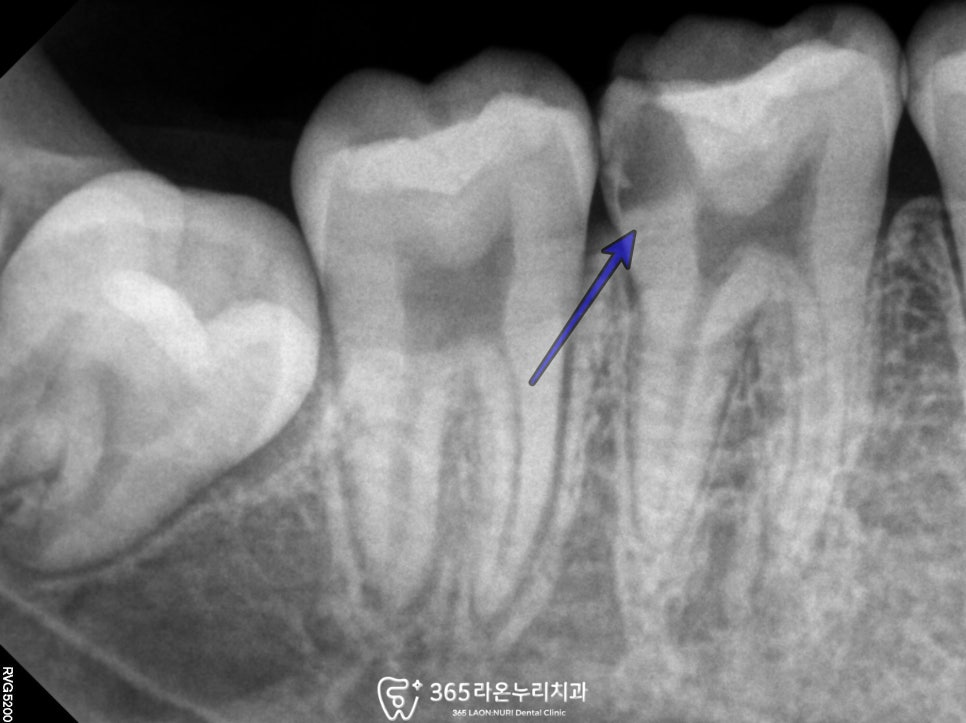

단순히 기존 버찰을 제거하고

인레이나 크라운을 했다가는

차갑거나 뜨거운 자극을 차단하지 못하여

통증이 그대로 지속될 것이고,

이는 이미 균에 감염되어있는 상태라

불편 증상은 계속 남아있을 것입니다.

「 endo(=신경치료) 시작 」

치근에 엔도용 파일을 넣어

뿌리의 모양과 위치를 확인하는 과정을 가집니다.